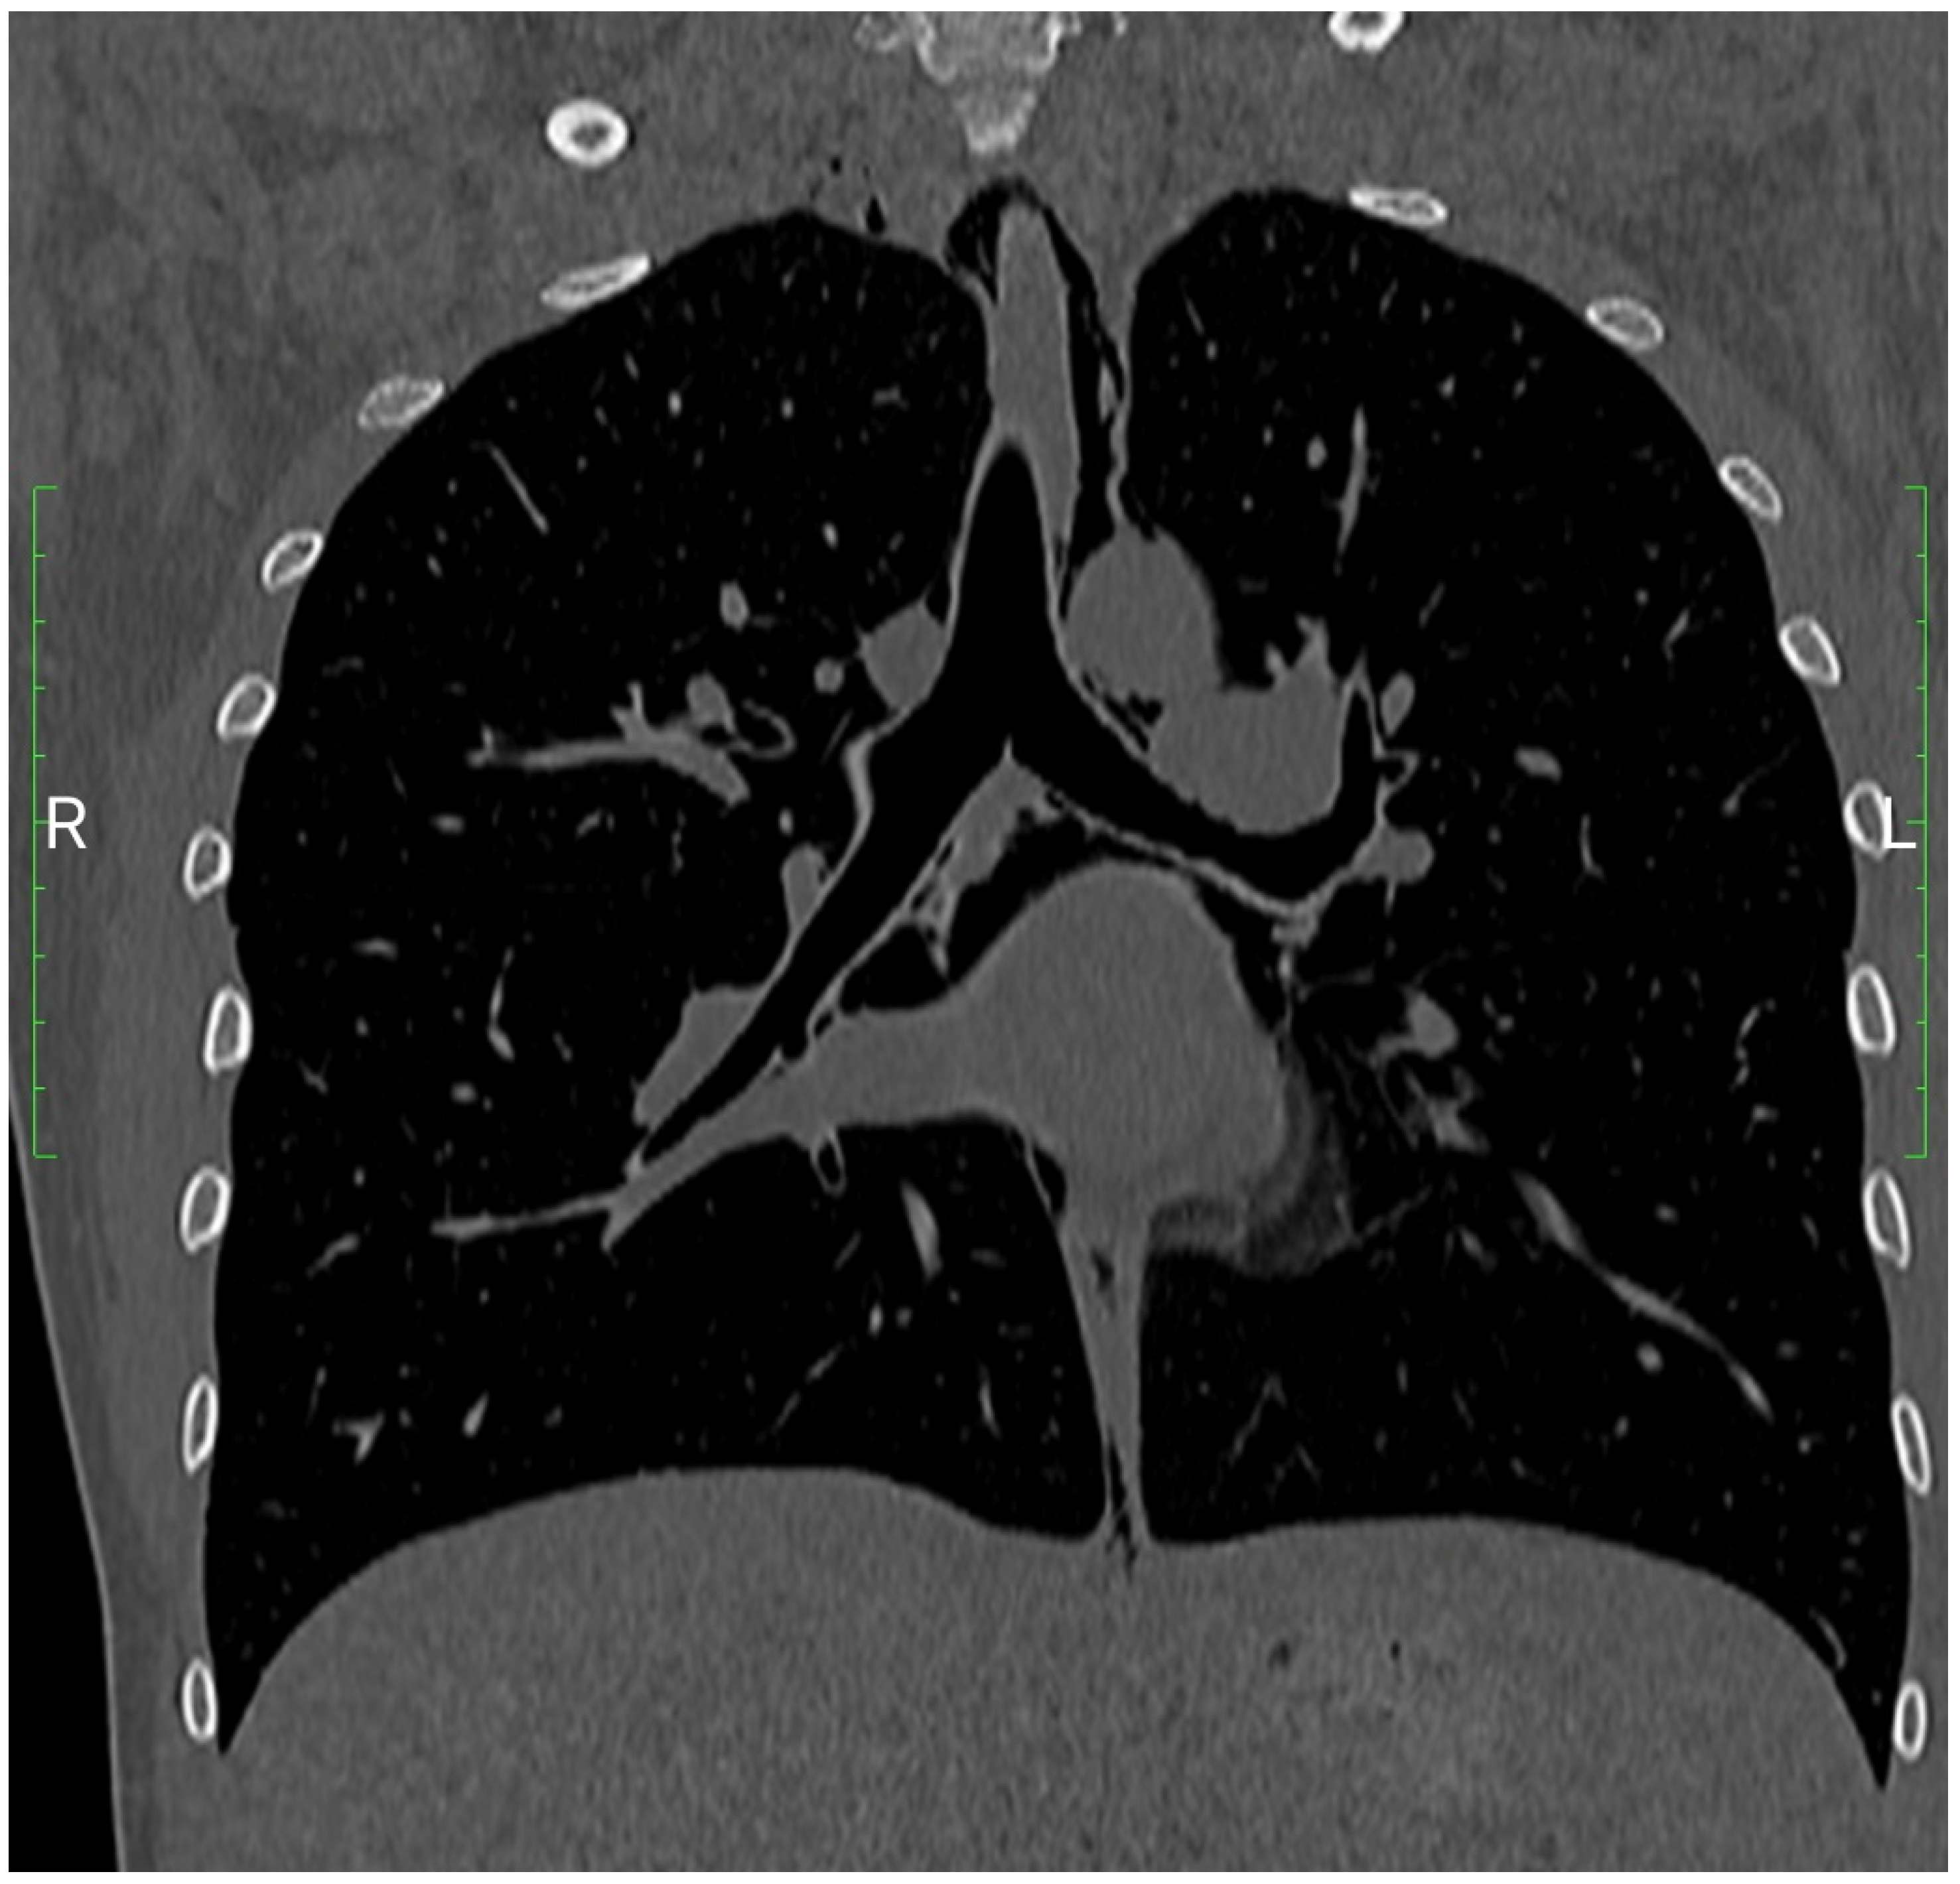

3.1. Case Report